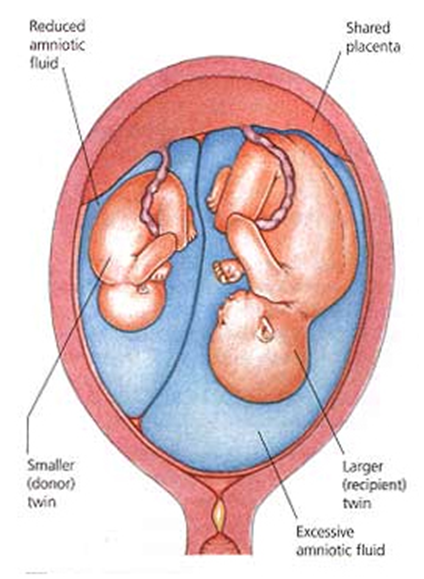

ட்வின்-டு-ட்வின்டிரான்ஸ்ஃப்யூஷன் சிண்ட்ரோம் (டிடிடிஎஸ்) நஞ்சுக்கொடியை (மோனோகோரியானிக் இரட்டையர்கள்) பகிர்ந்து கொள்ளும் ஒரேமாதிரியான இரட்டையர்களை பாதிக்கலாம்.

இரண்டு இரட்டையர்களையும் இணைக்கும்நஞ்சுக்கொடி இரத்தநாளங்களில் ஏற்றத்தாழ்வுஏற்பட்டால் TTTS நிகழ்கிறது. இரட்டையர்களுக்கு இடையில்இரத்தம் சீராகப்பாயவில்லை என்றால், ஒருவர் அதிக இரத்தத்தைப்பெறுகிறார், இதுபெறுநர் இரட்டை என்று அழைக்கப்படுகிறது, மற்றொன்று குறைவான இரத்தத்தைப்பெறுகிறது (தானம்செய்யும்இரட்டையர்).

சமச்சீரற்ற இரத்தஓட்டம், தானம் செய்பவர்களைவிட கூடுதல்ஊட்டச்சத்துக்கள் மற்றும்திரவம் காரணமாக, பெறுநரின்இரட்டையர் பெரிதாகவளர்கிறது.

பெறுநர்இரட்டை எடுக்கும் கூடுதல்திரவம் இதயத்தில் ஒரு அழுத்தத்தை ஏற்படுத்தும்.உடல் அதிகசிறுநீரை உற்பத்திசெய்வதன் மூலம்திரவத்தை அகற்றமுயற்சிக்கும். இதன்விளைவாக, பெறுநரிடம் அம்னோடிக் திரவம் அதிகமாக இருக்கும், அதேசமயம் நன்கொடையாளரிடம் சிறிதளவு அல்லது எதுவும் இருக்காது.

பெறுநரின் இரட்டை மற்றும் கூடுதல் திரவம்கருப்பையின் (கருப்பை) சுவருக்கு எதிராக நன்கொடையாளர் இரட்டையை அழுத்தலாம்.இதுதாய்க்கு அசௌகரியத்தைஏற்படுத்தலாம் மற்றும் சுருக்கங்கள் கூட ஏற்படலாம்.